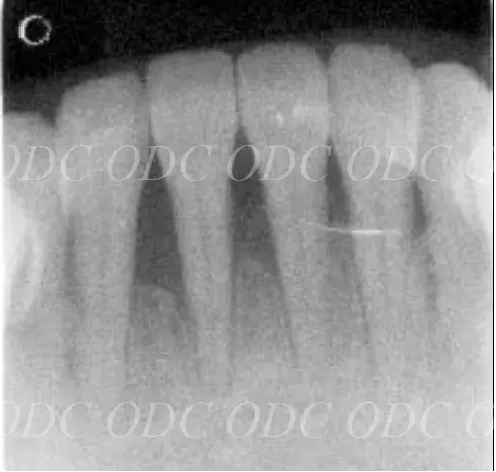

2008年、第一大臼歯の歯根破折を主訴に来院された。

サイナスリフト後にインプラント埋入。

左は術前のレントゲン写真。中央、右は2024年、術後約16年後のレントゲン写真と口腔内写真。

1枚目上、奥歯2本欠損でインプラント治療を希望された。サイナスリフト後、インプラント埋入。

2枚目、術後約10年経過。レントゲン的にも経過良好です。